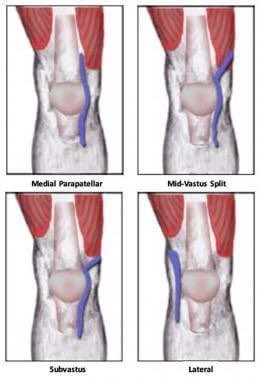

فالأصل وجميع الطرق الجراحية لا تعتمد على قطع الوتر

فلايوجد جراح يقوم بقطع وتر العضلة الرباعية (quadriceps muscle tenotomy)

كما يشاع بوجود طرق واكتشافات

وفي هذه الصورة ملخص الطرق الجراحية للوصل لغضاريف المفصل المتآكلة، طبعاً من دون قطع الوتر الاساسي للركبة

فلكل طريقة لها ميزات وعيوب

تعتمد على مهارات الجراح واختصاصه في هذا النوع من العمليات